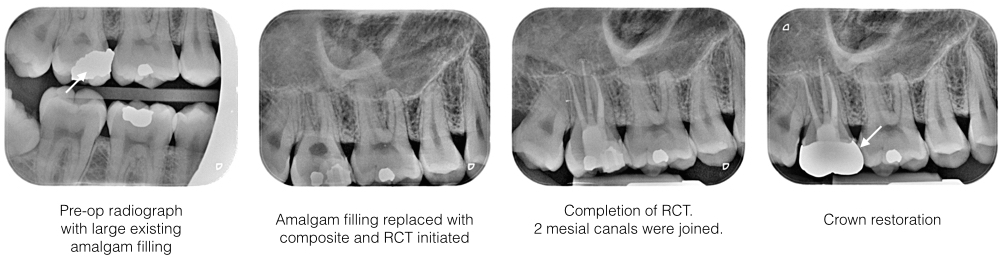

History : Patient is a 28 year old gentleman, presented with pain on upper right molar on chewing. Of late, the tooth is very sensitive to hot drinks.

Examination : Tooth 17 has a large old amalgam restoration. Bite test was positive whereby pain was noted upon releasing of bitting pressure. Cold test is positive suggesting the tooth is still vital. There was a hairline crack noted under microscope upon removing of old amalgam filling

Diagnosis : Acute apical periodontirs 17 due to crack tooth.

Treatment : Old amalgam restoration was replaced with composite filling and RCT was carried out under rubber dam isolation. Under microscope, all 4 root canals (MB1, MB2, DB, P canals) were located shaped, cleaned and obturated up to full working length. The tooth was subsequently restored with a semi precious metal crown.

RCT Case 4